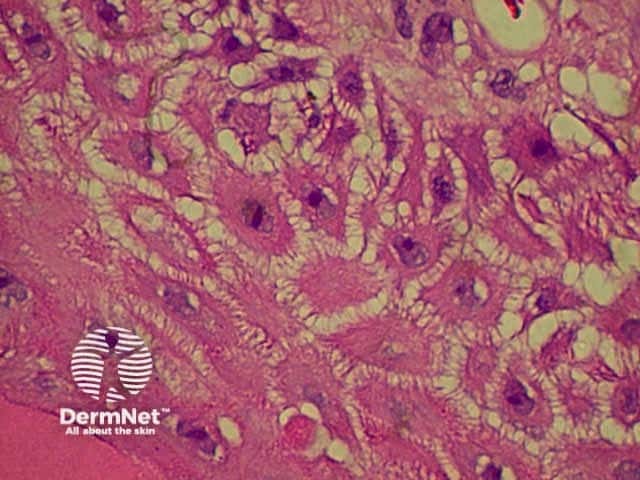

Bullous pemphigoid is the most common subepidermal blistering disease. Link to a clinical description of bullous pemphigoid.

The histological features of bullous pemphigoid are:

Direct immunofluorescence reveals IgG and complement deposits in the basement membrane zone. (Biopsies for fluorescence should ideally be taken from erythematous but not yet bullous areas.) Indirect immunofluorescence will detect circulating antibodies. ELISA will be positive to 180 and 230kd BP antigens 2 and 1 respectively. Using skin separated by a salt splitting process, immunoreactants are seen to bind to the roof of the blister.

Bullous pemphigoid Bullous pemphigoid Bullous pemphigoid